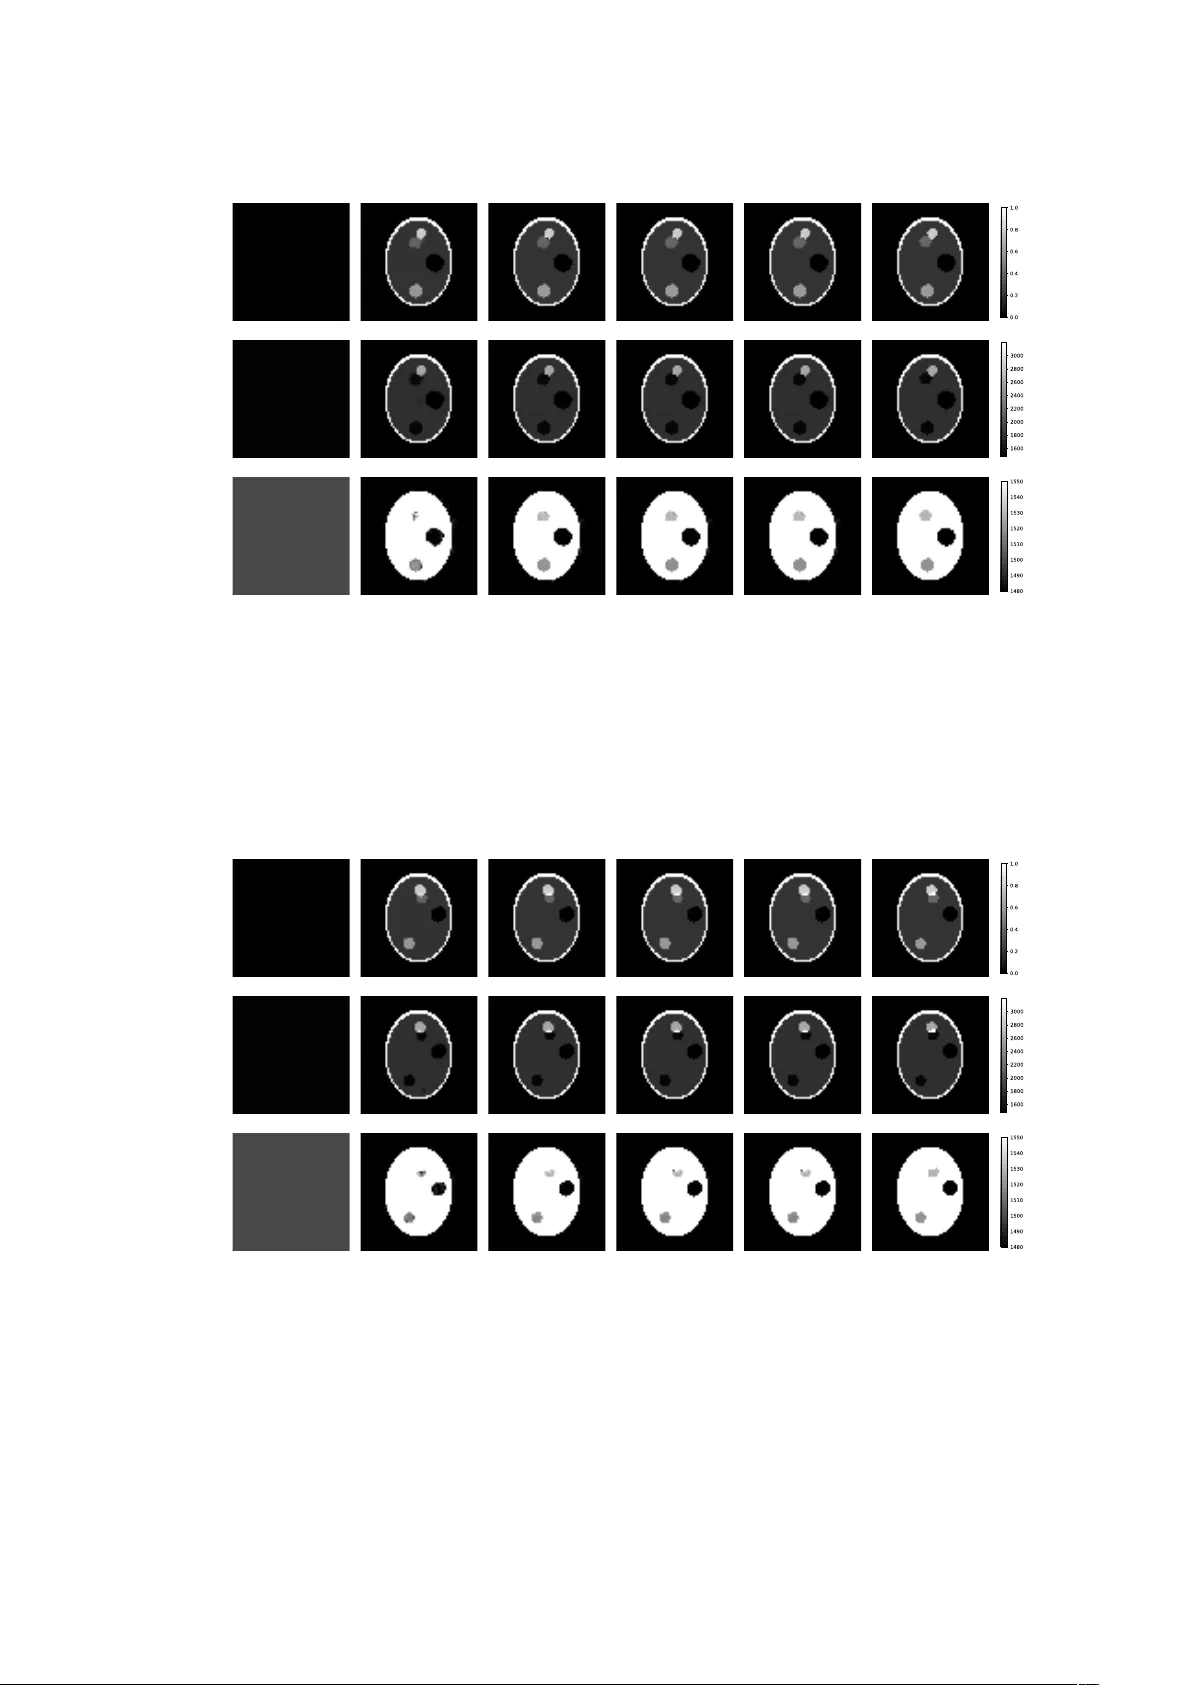

Simultaneous reconstruction of the initial pressure and sound speed in photoacoustic tomograph y using a deep-l earning approach Hongming Shan, Christopher Wiedeman, Ge W ang, Y ang Y ang Contact: shanh@rpi.edu, wiedec@rpi.edu, wangg6@rpi.edu, yangy5@msu.edu Rensselaer Pol ytechnic Institute Michigan State Univ ersity September 16, 2019 Abstract Photoacoustic tomography seeks to reconstruct an acoustic initial pressure distribution from the mea- surement of the ultrasound wa veforms. Conventional methods assume a-prior know ledge of the sound speed distribution, which practically is unkno wn. One way to circum vent the issue is to simultaneously reconstruct both the acoustic initial pressure and speed. In this article, we develop a novel data-driven method that integrates an advanced deep neural network through model-based iteration. The image of the initial pressure is significantly improved in our numerical simulation. 1 Introduction Photoacoustic tomography (P A T) is an emerging non-invasiv e modality that has manifested an enormous prospect for clinical practices [ 1 ]. In P A T , the tissue is illuminated with near- infrared light of wav elength 650-900nm. The absorbed optical energy is transformed into acoustic energy through the photoacoustic effect, and the generated ultrasound is measured by transducer arrays around the tissue in order to retrieve the optical internal proper- ties. The coupling mechanism of the optical and ultrasound waves gives multiple advantages ov er conv entional standalone modalities. For instance, the acoustic wave experiences less scattering in tissue compared to optical wav e, allowing P A T to break the optical diffusion limit and generate high-resolution images [2] while preserving intrinsic optical contrast [3]. T ypical photo-acoustic signal generation comprises three steps: (1) the tissue absorbs light; (2) the absorbed optical energy heats the tissue and raises the temperature; (3) thermo-elastic expansion occurs and generates ultrasound. The image formation in P A T is to recover the distribution of the deposited energy, known as the local optical fluence, from the ultrasound signals that are recorded by the sensors deploy ed around the tissue. As the initial ultrasound pressure is approximately proportional to the optical fluence, it is sufficient to reconstruct the initial pressure from the recorded ultrasound signals. Conventional reconstructive schemes, such as back -projection based methods [ 4 , 5 , 6 , 7 , 8 , 9 , 10 , 11 ] and time-rev ersal based methods [ 12 , 13 , 14 , 15 , 16 , 17 , 18 , 19 , 20 , 21 , 22 , 23 , 24 ], typically assume the sound speed is precisely known. This assumption howev er is not always fulfilled, and the precise sound speed distribution is often unknown. It is therefore of practical significance to study simultaneous reconstruction of both the sound speed distribution and the acoustic initial pressure. The purpose of this article is to address this issue using a data-driven approach. Data-driven approaches such as machine learning and deep learning have gained increasing attention recently in medical image reconstruction [ 25 , 26 ]. The powerful computational capacity of modern super computers has enabled these methods to enhance medical image reconstruction by extracting the hidden patterns in the data that would otherwise be lost. In P A T , data driven methods have achieved state-of -the-art results in P A T image reconstruction in the scenarios of sparse 1 data [ 27 , 28 , 29 ], limited view [ 30 , 31 , 32 ], artifacts removal [ 33 , 34 , 35 ], as well as other applications [ 36 , 37 , 38 ]. In addition to P A T , data-driven approaches hav e also found broad application in the image reconstruction of many other imaging modalities such as Computed T omograp hy (CT), Magnetic Resonance Imaging (MRI), as well as other related fields like radiomics and radiotheraphy , see [ 39 , 40 , 41 , 42 , 43 , 44 , 45 , 46 , 47 , 48 , 49 , 50 ] for some examples and applications along these directions. 2 Preliminary In this section, we formulate the mathematical model of the simultaneous reconstruction problem in P A T and review the recent advances based on model-driven approaches. Propagation of ultrasound in P A T is typically modeled as an initial value problem for the wav e equation. This can be written as ρ ( r ) ∂ u ∂ t ( r , t ) + ∇ p ( r , t ) = 0 , in (0 , T ) × R d 1 ρ ( r ) c ( r ) 2 ∂ p ∂ t ( r , t ) + ∇ · u ( r , t ) = 0 , in (0 , T ) × R d p ( r , 0) = p 0 ( r ) , u ( r , 0) = 0 , (1) where d = 2 , 3 is the dimension, u is the acoustic velocity, p is the acoustic pressure, T > 0 is the stoppage time of the measurement, ρ is the mass density, c is the sound speed, and p 0 is the initial pressure distribution. W e remark that another popular model in P A T is to deal with the second order acoustic equation rather than the abov e first order system. These models are more or less equivalent under suitable assumptions. Let Ω be a bounded domain in R d representing the tissue, with the boundary of Ω denoted by ∂ Ω . The measurement in P A T is the detected ultrasound signals, that is the temporal boundary data p | [0 ,T ] × ∂ Ω . W e further introduce a measurement map Λ which is defined as Λ : ( c, p 0 ) 7→ p | [0 ,T ] × ∂ Ω (2) where p is the solution of (1) . Assuming the mass density ρ is known, then the simultaneous reconstruction problem in PA T can be recast as the inverse problem to recover the pair ( c, p 0 ) from p | [0 ,T ] × ∂ Ω ; in other words, to invert the operator Λ . Note that Λ is linear in p 0 but non-linear in c . W e recall some known results regarding the simultaneous reconstruction in P A T . Linearization of the map (2) at sufficiently smooth pairs is studied in [ 51 ] and the linearized inversion is shown to be unstable in any scale of Sobolev spaces. Invertibility of Λ is established in [ 52 ] for radially symmetric sound speeds in any odd dimension higher than three; in [ 53 , 54 ] for sound speeds that satisfy certain orthogonality relation with harmonic functions. Numerical simulations have been implemented in [ 55 ] using the finite element model, and in [ 56 , 57 , 58 ] for parametrized sound speeds. Our data-driven approach is inspired by the work of Matthews et al. [ 56 ], where the authors proposed a direct optimization approach towards the simultaneous reconstruction, with the sound speed being confined in a parametrized lower -dimensional space. W e denote the measurement by g for simplicity . With slight abuse of notations, the discretized versions of p 0 and c are still denoted by themselves, which are two matrices. For a fixed sound speed c , the operator Λ( c, · ) is linear, hence its discretization is another matrix, say H ( c ) . The idea in Ref [56] is to minimize the objective function c p 0 , b c = arg min p 0 ≥ 0 , c ≥ 0 F ( p 0 , c ) + β R ( p 0 ) (3) where the data fidelity term is defined as F ( p 0 , c ) := 1 2 k g − H ( c ) p 0 k 2 and R denotes the regularization term for the initial pressure. This objective function can be solved using the proximal optimization method that allows constraints and nonsmooth regularization function for the initial pressure distribution. The initial pressure distribution and sound speed distribution are updated iteratively using gradient descent. The algorithm in Ref [ 56 ] is summarized in Algorithm 1 below . 3 Simultaneous Reconstruction via Deep Learning W e describe our data-driven method in this section. The motivation stems from some limitations of the iterative algorithm 1. For instance, repeated selection of step sizes to update the initial pressure and sound speed is time- 2 Algorithm 1 Simultaneous Reconstruction by iterative algorithm [56] Require: p (0) 0 , c (0) , β Ensure: b p 0 , b c 1: k ← 0 2: while stopping criterion is not satisfied do 3: Calculate gradients ∇ p 0 F and ∇ c F 4: Choose step length α p k and α c k 5: p ( k +1) 0 = pro x α p k β R p ( k ) 0 − α p k ∇ p 0 F 6: c ( k +1) = c ( k ) − α c k ∇ c F 7: k ← k + 1 8: end while 9: b p 0 ← p ( k +1) 0 10: b c ← c ( k +1) consuming; selection of the parameter β and the regularization term R is highly empirical; tuning β can be tedious. T o over come these limitations, we propose a simultaneous reconstruction network (SR-N et) to update the initial pressure and the sound speed for each iteration. 𝒑 𝟎 (𝒌) −𝜵 𝒑 𝟎 𝑭 𝒄 (𝒌) Conv ReLU Conv ReLU Conv ReLU Conv ReLU BN 𝒑 𝟎 (𝒌%𝟏) 𝒄 (𝒌%𝟏) Conv ReLU Conv ReLU Conv ReLU Conv ReLU ReLU Conv ReLU Conv BN ⊕ ReLU Conv ReLU Conv BN ⊕ Feature Ex traction Feature Fusi on Reconstruc tion Figure 1: The proposed simultaneous reconstruction network (SR-N et) for P A T . The proposed SR-Net is shown in Fig. 1. It contains three steps - feature extraction, feature fusion, and reconstruction. 1. F eature extraction: W e used two convolutional layers to extract features from the initial pressure dis- tribution, the negative gradient of data fidelity with respect to initial pressure, and current sound speed distribution. 2. F eature fusion: The feature maps extracted from above three branches are concatenated along the channel dimension, which are then fed into the batch normalization (BN) layer . Since the feature maps from the initial pressure and the sound speed are in different scale, this batch normalization layer can normalize feature maps into the same scale for subsequent feature fusion. The feature fusion part also contains two convolutional lay ers follow ed by ReL U. 3. Reconstruction: After the feature fusion, we use two convolutional layers to reconstruct the updated initial pressure and sound speed, respectively . A batch normalization lay er is used after first convolutional 3 layer to scale the fused feature back to the original scale. A skip connection after the second convolutional layer enables the network to learn the residual just like the traditional iterative algorithm (see step 5-6 in Algorithm 1). The last ReLU activation function guarantees the updated initial pressure and speed distribution are non-negative. T able 1: Network architectures of feature extraction, feature fusion, and reconstruction in SR-Net. Lay er F eature Extraction × 3 Featur e Fusion Reconstruction × 2 1 3 × 3 conv , 32, stride 1 Batch Normalization 3 × 3 con v , 16, stride 1 2 3 × 3 conv , 32, stride 1 3 × 3 conv , 64, stride 1 Batch Normalization 3 3 × 3 conv , 32, stride 1 3 × 3 conv , 1, stride 1 A detailed network structure is shown in T able 1. Note that zero-padding is used such that all feature maps have the same as the inputs. For each iteration, we trained SR- Net using the simulated dataset. At the k -th iteration, the loss function is chosen as follows: min θ SR E ( p ( k ) 0 , −∇ p 0 F,c ( k ) ,p 0 ,c ) p ( k +1) 0 − p 0 + 1 1000 c ( k +1) − c s.t. p ( k +1) 0 , c ( k +1) = SR-N et ( p ( k ) 0 , −∇ p 0 F , c ( k ) ) (4) where θ SR represents the parameters of the SR-N et. p 0 and c are the ground-truth labels. W e employ the Adam algorithm [ 59 ] to update the parameters in θ SR . The gradients of the parameters are computed using a back - propagation algorithm. The iterative reconstruction algorithm is summarized in Algorithm 2. Algorithm 2 Simultaneous reconstruction via Deep learning Require: p (0) 0 , c (0) , k max Ensure: b p 0 , b c 1: k ← 0 2: while k < k max do 3: Calculate gradient ∇ p 0 F 4: p ( k +1) 0 , c ( k +1) = SR-N et ( p ( k ) 0 , −∇ p 0 F , c ( k ) ) 5: k ← k + 1 6: end while 7: b p 0 ← p ( k +1) 0 8: b c ← c ( k +1) Note that our proposed network is different from the model in Ref [ 30 ] because 1) our network aims to reconstruct the initial pressure distribution and sound speed distribution simultaneously, while the model in Ref [ 30 ] assumes the sound speed is precisely known; 2) our network is a 2D network, while the model in Ref [ 30 ] is a 3D network; and 3) the proposed network used the batch normalization lay er to scale the feature maps, while the model in Ref [30] used an explicit coefficient to represent the step length. 4 RESUL TS 4.1 Data generation In this study , we used a simplified Shepp-logan phantom to train and test our network. Fig. 2 shows the phantom along with the initial pressure and the sound speed distribution. W e randomly changed the sizes and positions of the region 1, 3, 4, and 5 in order to increase the diversity of dataset. The corresponding initial pressure and sound speed are shown in T able 2. W e put the phantom into a 64 × 64 image, which is surrounded by 252 detectors in the rectangle form. For the training purpose, we randomly generated 5,120 images with acoustic signal of the size 252 × 652 . The mass density is assumed to be constant 1 throughout. Then we selected 1,024 images randomly to test the trained model. 4 1 2 3 4 5 6 (b) (a) (c) Figure 2: An example of phantom, initial pressure and sound speed. The phantom used in this study contains 6 regions (a ), which was filled with different initial pressure shown in (b). The corresponding sound speed distribution is shown in (c ). Note that the yellow background in ( a) denotes the outside of the phantom. T able 2: The initial pressure and sound speed for each region. Index Initial Pressure Sound Speed [m/ s] 1 0.0 1480 2 0.2 1800 3 0.4 1530 4 0.6 1520 5 0.8 2600 6 1.0 3198 4.2 Experimental results Throughout the experiments, the initial pressure was initialized uniformly as zero and the sound speed was initialized uniformly as 1,500 m/ s. The maximum number of iteration k max was set to 4. The gradient of the data fidelity with respect to the initial pressure is computed by the adjoint state method using the k -w ave package [ 60 ]. The proposed SR-N et was implemented by Pytorch and trained on four NVIDIA 1080Ti GPUs. W e show two testing images in Figs. 3 and 4, which were not used in training stage. It is observed that the proposed method can reconstruct the initial pressure and sound speed simultaneously with very high accuracy . Mean absolute error for sound speed and initial pressure were calculated for each reconstructed image at each iteration. The average value and standard deviations of these errors are contained in T able 3. T able 3: Mean absolute error of the initial pressure and sound speed distribution for each iteration in the form of MEAN ± STD . Mean Absolute Error Iter 1 Iter 2 Iter 3 I ter 4 p (1.43 ± 0.36) × 10 − 2 (0.86 ± 0.33) × 10 − 2 (0.85 ± 0.33) × 10 − 2 (0.85 ± 0.33) × 10 − 2 c [m/ s] 3.13 ± 0.64 1.33 ± 0.52 1.25 ± 0.52 1.24 ± 0.52 4.3 Generalization ability of the trained SR- Net on a new phantom All Shepp-Logan phantoms used to train the model featured all six regions listed in T able 2. T o test the generaliz- ability of the model, we reconstructed four phantoms with region 5 remov ed. Figures 5 and 6 illustrate two cases of this test. From these cases, it can be observed that the model still accurately reconstructs phantoms that contain less regions than the phantoms used to train the model. 5 p c c Initial Iter 1 Iter 2 Iter 3 Iter 4 GT Figure 3: The first case of the simultaneously reconstructed results by applying SR- Net to the same phantom. The first row shows the initial pressure. The second and third rows show the sound speed distribution in range of [1480, 3198] and of [1480, 1550 ], respectively . GT means the ground-truth. p c c Initial Iter 1 Iter 2 Iter 3 Iter 4 GT Figure 4: The second case of the simultaneously reconstructed results by applying the SR-N et to the same phantom. The first row shows the initial pressure. The second and third rows show the sound speed distribution in the range of [1480, 3198] and of [1480, 1550], respectively . GT means the ground-truth. 6 p c c Initial Iter 1 Iter 2 Iter 3 Iter 4 GT Figure 5: The first case of the simultaneously reconstructed results by applying the SR-N et to the new phantom. The first row shows the initial pressure. The second and third rows show the sound speed distribution in the range of [1480, 3198] and of [1480, 1550], respectively . GT means the ground-truth. p c c Initial Iter 1 Iter 2 Iter 3 Iter 4 GT Figure 6: The second case of the simultaneously reconstructed results by applying the SR-N et to the new phantom. The first row shows the initial pressure. The second and third rows show the sound speed distribution in the range of [1480, 3198] and of [1480, 1550], respectively . GT means the ground-truth. 7 5 Discussions and Conclusion The main weakness of this study is the numerical nature, which may not fully reflect all the physical factors in real clinical/pre-clinical applications. W e plan to perform physical phantom experiments as a next step. Also, we are interested in animal studies in vivo. Nev ertheless, the numerical results and the network trained with simulated data may serve a baseline for further improvements. Hopefully , this imaging modality may find practical use in some important tasks such as breast imaging. In conclusion, we have developed a simultaneous reconstruction network (SR- Net) to jointly recover the sound speed and initial pressure in photoacoustic tomography . The proposed SR-N et has several merits: automatically learning the step size, regularization term, and the trade-off between data fidelity and regularization in a data- driven manner, and not requiring the gradient of the data fidelity with respect to sound speed. In the future, we will further improve the structure of the network and also validate it on more complicated datasets. 6 Ackno wl edgment The research of Y . Y ang is partly supported by the NSF grant DMS-1715178, the AMS-Simons travel grant, and the startup fund from Michigan State University . The authors would like to thank NVIDIA Corporation for the donation of GPU used for this research. Ref erences [1] Jun Xia, J unjie Y ao, and Lihong V W ang. Photoacoustic tomograph y: principles and advances. Electromagnetic waves ( Cambridge, Mass.) , 147:1, 2014. [2] Lihong V W ang and Gene K Beare. Breaking the optical diffusion limit: Photoacoustic tomography . In Frontiers in Optics , page FWY2. Optical Society of America, 2010. [3] Junjie Y ao and Lihong V W ang. Photoacoustic tomograph y: fundamentals, advances and prospects. Contrast media & molecular imaging , 6(5):332–345, 2011. [4] David Finch, Rakesh, and Leonid Kun yansky. Recov ering a function from its spherical mean values in two and three dimensions. Photoacoustic Imaging and Spectroscopy , 2009. [5] David Finch, Markus Haltmeier , and Rak esh. Inversion of spherical means and the wa ve equation in even dimensions. SIAM Journal on Applied Mathematics , 68(2):392–412, 2007. [6] Markus Haltmeier, Thomas Schuster, and Otmar Scherzer. Filtered backprojection for thermoacoustic computed tomography in spherical geometry . Mathematical methods in the applied sciences , 28(16):1919–1937, 2005. [7] Robert A Kruger, Daniel R Reineck e, and Gabe A Kruger. Thermoacoustic computed tomography –technical considerations. Medical physics , 26(9):1832–1837, 1999. [8] Robert A Kruger, William L Kiser Jr, Daniel R Reineck e, and Gabe A Kruger. Thermoacoustic computed tomography using a conventional linear transducer array . Medical physics , 30(5):856–860, 2003. [9] Leonid A Kuny ansky. Explicit inversion formulae for the spherical mean Radon transform. Inverse problems , 23(1):373, 2007. [10] Minghua Xu and Lihong V W ang. Universal back -projection algorithm for photoacoustic computed tomog- raphy . Physical Review E , 71(1):016706, 2005. [11] Y uan Xu, Lihong V W ang, Gaik Ambartsoumian, and P eter Kuchment. R econstructions in limited-view thermoacoustic tomography . Medical physics , 31(4):724–733, 2004. [12] Eric Chung, Chi Y eung Lam, and Jianliang Qian. A Neumann series based method for photoacoustic tomography on irregular domains. Contemporary Mathematics , 615:89–104, 2014. 8 [13] Benjamín Palacios. Reconstruction for multi-wav e imaging in attenuating media with large damping coeffi- cient. Inverse Problems , 32(12):125008, 2016. [14] Andrew Homan. Multi-wa ve imaging in attenuating media. Inverse Problems & Imaging , 7(4):1235–1250, 2013. [15] Y ulia Hristova. Time reversal in thermoacoustic tomography—an error estimate. Inverse Problems , 25(5):055008, 2009. [16] Y ulia Hristova, P eter Kuchment, and Linh Nguyen. Reconstruction and time reversal in thermoacoustic tomography in acoustically homogeneous and inhomogeneous media. Inverse Problems , 24(5):055006, 2008. [17] Jianliang Qian, Plamen Stefano v, Gunther Uhlmann, and Hongkai Zhao. An efficient Neumann series–based algorithm for thermoacoustic and photoacoustic tomography with variable sound speed. SIAM Journal on Imaging Sciences , 4(3):850–883, 2011. [18] Plamen Stefanov and Gunther Uhlmann. Thermoacoustic tomography with variable sound speed. Inverse Problems , 25(7):075011, 2009. [19] Plamen Stefanov and Gunther Uhlmann. Thermoacoustic tomography arising in brain imaging. Inverse Problems , 27(4):045004, 2011. [20] Plamen Stefanov and Y ang Y ang. Multiwa ve tomography in a closed domain: averaged sharp time reversal. Inverse Problems , 31(6):065007, 2015. [21] Plamen Stefanov and Y ang Y ang. Thermo-and photoacoustic tomography with variable speed and planar detectors. SIAM Journal on Mathematical Analysis , 49(1):297–310, 2017. [22] Plamen Stefanov and Y ang Y ang. Multiwav e tomography with reflectors: Landweber’s iteration. Inverse Problems & Imaging , 11(2):373–401, 2017. [23] Zakaria Belhachmi, Thomas Glatz, and Otmar Scherzer. A direct method for photoacoustic tomography with inhomogeneous sound speed. Inverse Problems , 32(4):045005, mar 2016. [24] Ashkan Javaherian and Sean Holman. Direct quantitative photoacoustic tomography for realistic acoustic media. Inverse Problems , 2019. [25] Ge W ang. A perspective on deep imaging. IEEE Access , 4:8914–8924, 2016. [26] Ge W ang, Jong Chu Y e, Klaus Mueller, and J effrey A Fessler. Image reconstruction is a new frontier of machine learning. IEEE transactions on medical imaging , 37(6):1289–1296, 2018. [27] Stephan Antholzer, Markus Haltmeier, and Johannes Schwab. Deep learning for photoacoustic tomography from sparse data. Inverse Problems in Science and Engineering , 27(7):987–1005, 2019. [28] Stephan Antholzer, Markus Haltmeier , Robert Nuster, and Johannes Schwab. Photoacoustic image recon- struction via deep learning. In Photons Plus Ultrasound: Imaging and Sensing 2018 , volume 10494, 2018. [29] Stephan Antholzer, Johannes Schwab, and Markus Haltmeier . Deep learning versus ` 1 -minimization for compressed sensing photoacoustic tomograph y. In 2018 IEEE International Ultrasonics Symposium (IUS) , pages 206–212. IEEE, 2018. [30] Andreas Hauptmann, Felix Lucka, Marta M. Betck e, Nam Huynh, Jonas Adler, Ben T . Co x, Paul C. Beard, Sébastien Ourselin, and Simon R. Arridge. Model-based learning for accelerated, limited-view 3-D photoa- coustic tomography . IEEE T ransactions on Medical Imaging , 37(6):1382–1393, 2018. [31] Dominik W aibel, Janek Gröhl, F abian Isensee, Thomas Kirchner, Klaus Maier -Hein, and Lena Maier -Hein. Reconstruction of initial pressure from limited view photoacoustic images using deep learning. In Photons Plus Ultrasound: Imaging and Sensing 2018 , volume 10494, 2018. 9 [32] Johannes Schw ab, Stephan Antholzer, Robert Nuster, Günther Paltauf, and Markus Haltmeier. Deep learning of truncated singular values for limited view photoacoustic tomography . In Photons Plus Ultrasound: Imaging and Sensing 2019 , volume 10878, page 1087836. International Society for Optics and Photonics, 2019. [33] Steven Guan, Amir Khan, Siddhartha Sik dar, and Parag Chitnis. Fully dense UNet for 2D sparse photoacoustic tomography artifact removal. IEEE journal of biomedical and health informatics , 2019. [34] Derek Allman, Austin Reiter, and Muyinatu A Lediju Bell. Photoacoustic source detection and reflection artifact removal enabled by deep learning. IEEE transactions on medical imaging , 37(6):1464–1477, 2018. [35] Derek Allman, Austin Reiter, and Muyinatu Bell. Exploring the effects of transducer models when training convolutional neural networks to eliminate reflection artifacts in experimental photoacoustic images. In Photons Plus Ultrasound: Imaging and Sensing 2018 , volume 10494, page 104945H. International Society for Optics and Photonics, 2018. [36] Brendan Kell y, Thomas P Matthews, and Mark A Anastasio. Deep learning-guided image reconstruction from incomplete data. arXiv preprint , 2017. [37] Johannes Schwab, Stephan Antholzer, Robert Nuster, and Markus Haltmeier. Real-time photoacoustic projection imaging using deep learning. , 2018. [38] Hongming Shan, Ge W ang, and Y ang Y ang. A ccelerated correction of reflection artifacts by deep neural networks in photo-acoustic tomography . Applied Sciences , 9(13):2615, 2019. [39] Hu Chen, Yi Zhang, Y unjin Chen, Junfeng Zhang, W eihua Zhang, Huaiqiang Sun, Y ang L v , P eixi Liao, Jiliu Zhou, and Ge W ang. Learn: Learned experts’ assessment-based reconstruction network for sparse-data CT. IEEE transactions on medical imaging , 37(6):1333–1347, 2018. [40] Hongming Shan, Atul Padole, Fatemeh Homa younieh, Uwe Kruger, Ruhani Doda Khera, Chayanin Niti- warangkul, Mannudeep K Kalra, and Ge W ang. Competitive performance of a modularized deep neural network compared to commercial algorithms for low -dose CT image reconstruction. Nature Machine Intelli- gence , 1(6):269–276, 2019. [41] H Shan, Y Zhang, Q Y ang, U Kruger, MK Kalra, L Sun, W Cong, and G W ang. 3-D convolutional encoder - decoder network for low -dose CT via transfer learning from a 2-D trained network. IEEE T rans Med Imaging , 37(6):1522–1534, 2018. [42] Chenyu Y ou, Guang Li, Yi Zhang, Xiaoliu Zhang, Hongming Shan, Shenghong Ju, Zhen Zhao, Zhuiyang Zhang, W enxiang Cong, Michael W V annier, Punam K Saha, and Ge W ang. CT super-resolution GAN constrained by the identical, residual, and cycle learning ensemble (GAN-CIR CLE). IEEE T ransactions on Medical Imaging , 2019. [43] Huidong Xie, H ongming Shan, W enxiang Cong, Xiaohua Zhang, Shaohua Liu, Ruola Ning, and Ge W ang. Dual network architecture for few -view CT–trained on imagenet data and transferred for medical imaging. arXiv preprint arXiv:1907 .01262 , 2019. [44] Fenglei Fan, H ongming Shan, and Ge W ang. Quadratic autoencoder for low -dose CT denoising. In 15th International Meeting on Fully Three-Dimensional Image Reconstruction in Radiolog y and Nuclear Medicine , volume 11072, page 110722Z. International Society for Optics and Photonics, 2019. [45] Hongming Shan, Uwe Kruger, and Ge W ang. A novel transfer learning framework for low-dose CT. In 15th International Meeting on Fully Three-Dimensional Image Reconstruction in Radiolog y and Nuclear Medicine , volume 11072, page 110722Y. International Society for Optics and Photonics, 2019. [46] Qing Lyu, Hongming Shan, and Ge W ang. MRI super-resolution with ensemble learning and complementary priors. arXiv preprint arXiv:1907 .03063 , 2019. [47] Hongming Shan, Ge W ang, Mannudeep K Kalra, R de Souza, and Junping Zhang. Enhancing transferability of features from pretrained deep neural networks for lung nodule classification. In Proceedings of the 2017 International Conference on Fully Three-Dimensional Image Reconstruction in Radiology and Nuclear Medicine , 2017. 10 [48] Yiming Lei, Y ukun Tian, Hongming Shan, Junping Zhang, Ge W ang, and Mannudeep Kalra. Soft activation mapping of lung nodules in low -dose CT images. arXiv preprint , 2018. [49] Zhao Peng, Hongming Shan, Tianyu Liu, Xi Pei, Ge W ang, and X George Xu. MCDN et–a denoising convolu- tional neural network to accelerate Monte Carlo radiation transport simulations: A proof of principle with patient dose from x-ra y CT imaging. IEEE Access , 7:76680–76689, 2019. [50] Benjamin Q Huynh, Hui Li, and Maryellen L Giger. Digital mammographic tumor classification using transfer learning from deep convolutional neural networks. J ournal of Medical Imaging , 3(3):034501, 2016. [51] Plamen Stefanov and Gunther Uhlmann. Instability of the linearized problem in multiwave tomography of recov ery both the source and the speed. Inverse Problems & Imaging , 7(4):1367–1377, 2013. [52] David Finch and K yle S Hickmann. T ransmission eigenvalues and thermoacoustic tomography . Inverse Problems , 29(10):104016, 2013. [53] Hongyu Liu and Gunther Uhlmann. Determining both sound speed and internal source in thermo-and photo-acoustic tomography . Inverse Problems , 31(10):105005, 2015. [54] Christina Kno x and Amir Moradifam. Determining both the source of a wave and its speed in a medium from boundary measurements. arXiv preprint , 2018. [55] Zhen Y uan, Qizhi Zhang, and Huabei Jiang. Simultaneous reconstruction of acoustic and optical properties of heterogeneous media by quantitative photoacoustic tomography . Optics express , 14(15):6749–6754, 2006. [56] Thomas P Matthews, Joemini P oudel, Lei Li, Lihong V W ang, and Mark A Anastasio. Parameterized joint reconstruction of the initial pressure and sound speed distributions for photoacoustic computed tomography . SIAM journal on imaging sciences , 11(2):1560–1588, 2018. [57] Jin Zhang, Kun W ang, Y ongyi Y ang, and Mark A Anastasio. Simultaneous reconstruction of speed-of- sound and optical absorption properties in photoacoustic tomography via a time-domain iterative algorithm. In Photons Plus Ultrasound: Imaging and Sensing 2008: The Ninth Conference on Biomedical Thermoacoustics, Optoacoustics, and Acousto-optics , volume 6856, page 68561F . International Society for Optics and Photonics, 2008. [58] Thomas P Matthews and Mark A Anastasio. Joint reconstruction of the initial pressure and speed of sound distributions from combined photoacoustic and ultrasound tomography measurements. Inverse problems , 33(12):124002, 2017. [59] Diederik P Kingma and Jimmy Ba. Adam: A method for stochastic optimization. arXiv preprint , 2014. [60] B. E. T reeby and B. T. Co x. k -wa ve: MA TLAB toolbo x for the simulation and reconstruction of photoacoustic wav e-fields. Journal of Biomedical Optics , 15(2):021314, 2010. 11

Original Paper

Loading high-quality paper...

Comments & Academic Discussion